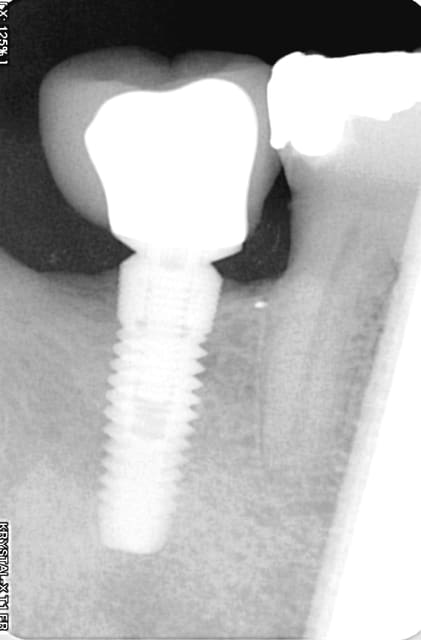

Voici 2 clichés radiologiques qui peuvent paraître surprenants (ici c'est un implant easyimplant à connexion type astra), le premier en juillet 2009 le jour de la pose de la couronne et le deuxième ce mois d'août 2011 (certes vous êtes obligé de me croire, mais ce n'est pas la première fois que j'observe ce phénomène). Ici, le patient procède à un contrôle de plaque parfait.

> Voici 2 clichés radiologiques qui peuvent paraître surprenants (ici c'est un

> implant easyimplant à connexion type astra), le premier en juillet 2009 le jour

> de la pose de la couronne et le deuxième ce mois d'août 2011 (certes vous êtes

> obligé de me croire, mais ce n'est pas la première fois que j'observe ce

> phénomène). Ici, le patient procède à un contrôle de plaque parfait.

Et bien moi je te crois tout à fait: l'os a tendance à croitre du fait de la stimulation et cela nous est caché (presque toujours) par l'agression bactérienne chronique, c'est ce que je crois.

growly vraiment super tes 2 radios